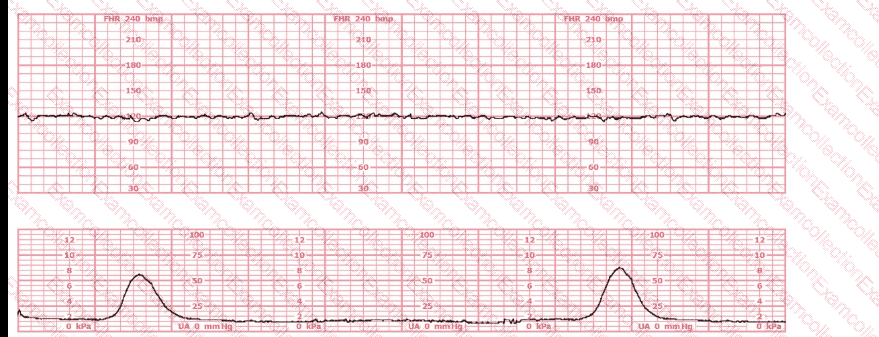

A 30-year-old woman (G2P0) is experiencing preterm labor at 26-weeks gestation. She is receiving magnesium sulfate for neuroprotection. Her external fetal monitoring tracing over the past 30 minutes is shown. The next step would be to: